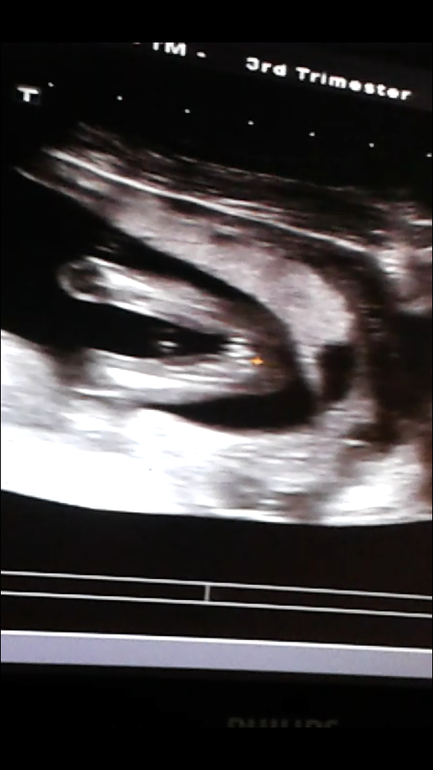

Ждём девочку)))))

Вертится с трудом, но видно всё было четко. Несколько раз поймали ракурс и все рассмотрели.

между ножек: